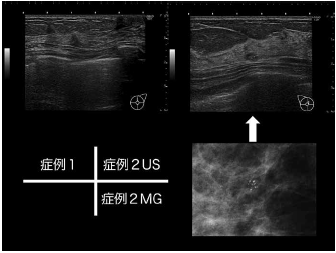

LOGIQ-E10の最大の特徴としては高性能のGPUを搭載し、cSoundというアルゴリズムを用いて全深度・全視野においてフルフォーカスされている点である。cSoundとは超音波ビームをオーバーラップさせることで、1つの反射源から複数の受信信号を取得する画期的なアルゴリズムのこと(図4 GEHC社提供)。これにより高精細な画像が得られている。乳房超音波診断において何よりも重要なのはB-mode画像である、とわれわれは位置付けている。したがってB-mode画像の画質向上は診断能に大きく影響すると考える。B-mode画像で小腫瘤径の腫瘤を精細に描出した超音波画像を示す(図5 症例1)。不整形低エコー腫瘤が認められ、病理組織は浸潤性乳管癌(硬性型)であった。

LOGIQ-E10の導入後の日々の臨床でわれわれが強く実感しているのは、石灰化の描出において以前の装置(LOGIQ-7)より圧倒的に優れていることであろう。症例2(図5 症例2)の超音波画像では、楕円形の腫瘤内に点状高エコーが明瞭に描出されているのがわかる。マンモグラフィ画像では、淡く不明瞭〜多形性の微細石灰化の集簇性分布を認められる。病理組織はDCIS(充実型)であった。

右上 症例2 楕円形低エコー腫瘤内の点状高エコーを描出した超音波画像

右下 症例2 淡く不明瞭〜多形性微細石灰化の集簇を呈したマンモグラフィ画像